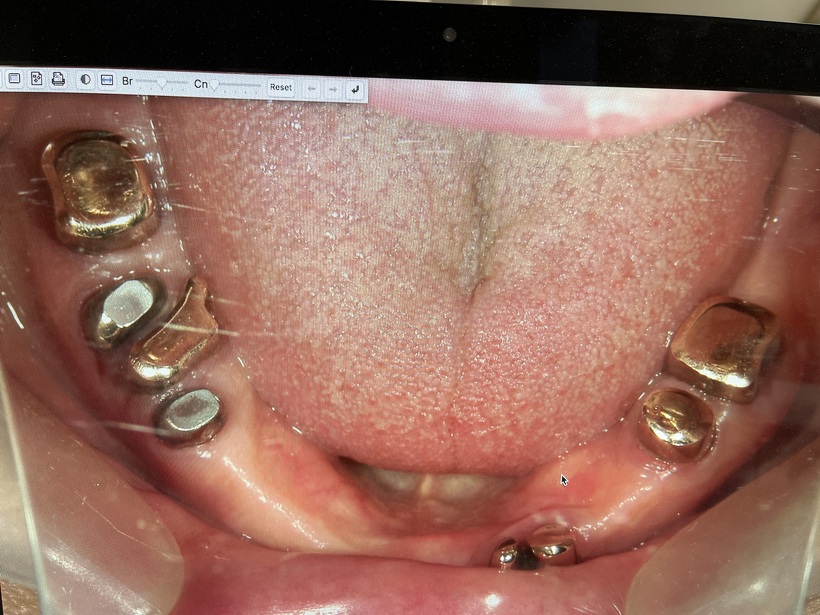

使用中の上総義歯 下コーヌスブリッジ義歯

治療の結果上下で10本が残りました。上顎は2本の歯を総義歯の中に組み込みました。下顎のコーヌスブリッジ義歯 8本の支台歯(実際は7本ですが右下6番は根を2つに分割して使用しています)で14本の歯を作りました。